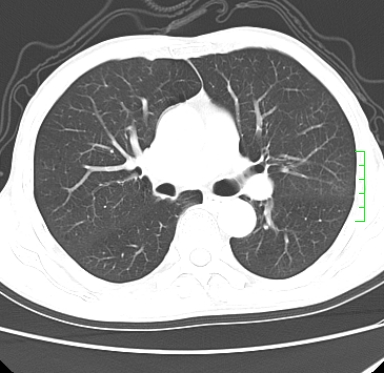

m,73y。膝关节疼痛伴双下肢水肿。入院常规胸片发现结节灶。增强为静脉期。

浅分叶、棘突,考虑右下肺周围型肺癌

肿块周围可见局限性气肿,考虑肺癌可能性大。双肺上叶继发型肺结核。

指套征,强化明显,近侧肺组织局限性肺气肿,考虑支气管类癌,慢支、肺气肿、双上陈旧性tb、冠脉钙化。

1)考虑右肺下叶周围型肺癌。2)右肺上叶及左肺感染性病变(结核可能)。3)肺气肿。4)冠状动脉钙化。